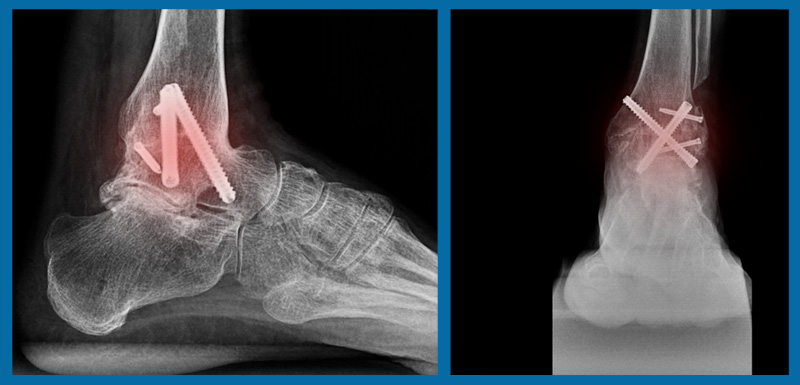

Hatta kısa mesafe koşabilir, araba kullanabilir. Yürümesinde aksama da olmaz. Fakat söylediğim durum, büyük kemik kaybı olmayan tek eklem sabitlemesi için geçerlidir. Üzülerek görmekteyim ki bazı meslektaşlarımız, sorun sadece ayak bileği ekleminde olsa bile kolaya kaçarak topuktan gönderilen uzun bir çiviyle ayak bileği sabitlemesi yapmaktadırlar. Bu durumda ayak bileği ile birlikte altındaki “subtalar” eklem de sabitlenmiş olur ki o zaman yürüyüş, tek eklem sabitlenmesindeki kadar rahat olmaz. Bu işlemi yine de mümkün olduğu kadar geç yapmak isteriz, en son seçenek olmalıdır, fakat tecrübeli ellerde yapıldığında korkulacak bir durum değildir.

Hayat kalitesini arttırır. Hem ayak bileğinin, hem de altındaki kemiğin sabitlenmesini gerektiren durumlar ayrıdır.